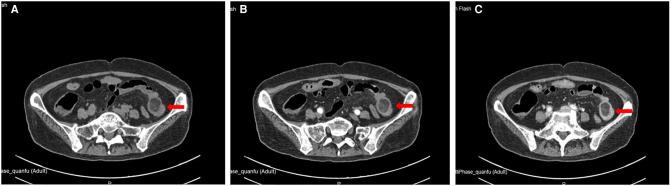

A 51-year-old female was admitted to the hospital with "abdominal pain for 1 month." Enhanced computed tomography (CT) of the abdomen suggested a lipoma in the left lower quadrant and a proximal intussusception. After excluding surgical contraindications, laparoscopic exploration was performed on the second day of admission, which showed a small amount of ascites in the abdominal cavity, a small intestine-small intestine-type intussusception about 20 cm from the ileocecal area and about 140 cm from the ileocecal area, and a mass of about 2×4 cm that was palpable by laparoscopic intestinal forceps, which was protruded into the intestinal cavity with a soft texture and sound mobility. A 5 cm-long incision was made above the mass to dissect into the abdomen layer by layer, and the diseased intestine was dislodged outside the abdominal cavity with oval forceps. The intestine was reduced by hand and observed for half an hour after reduction, and the blood circulation and peristalsis of the intestine were observed to be still sound. The intestine was dissected at 2 cm from the upper and lower margins of the mass using linear anastomosis to operate small intestine side-to-side anastomosis. The intestine was opened concurrently and closed with a linear anastomosis, using 3-0 absorbable thread to reinforce anastomosis intermittently. The procedure went smoothly, and the patient was discharged on the 5th postoperative day.

一名51岁女性因“腹痛1个月”入院。腹部增强计算机断层扫描(CT)显示左下腹有一个脂肪瘤,近端肠套叠。排除手术禁忌证后,于入院第二天进行腹腔镜探查,结果显示腹腔内有少量腹水,距回盲部约20 cm和距回盲部约140 cm处为小肠-小肠型肠套叠,腹腔镜肠钳可触及一个约2×4 cm的肿物,该肿物突入肠腔,质地柔软,活动度良好。在肿物上方做一个5 cm长的切口,逐层切开进入腹腔,用卵圆钳将病变肠管移出腹腔。手动复位肠管,复位后观察半小时,观察到肠管血液循环和蠕动仍良好。在距肿物上下边缘2 cm处切断肠管,采用直线吻合器行小肠侧侧吻合。同时打开肠管,用直线吻合器关闭,用3-0可吸收缝线间断加固吻合。手术过程顺利,患者术后第5天出院。